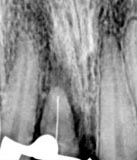

Se tomó radiografía panorámica (fig. 1) encontrando que el tercer molar superior derecho está erupcionado y el ápice cerrado, no teniendo antagonista y estando fuera de oclusión. Además de la periapical de la región anterior (fig. 1a).

Fig. 1 Se observa pieza 1.8 erupcionada, ápice cerrado, fuera de oclusión, ausencia de antagonista

fig. 1ª: En la radiografía periapical se observa una espiga demasiado ancha y sobreobturación.